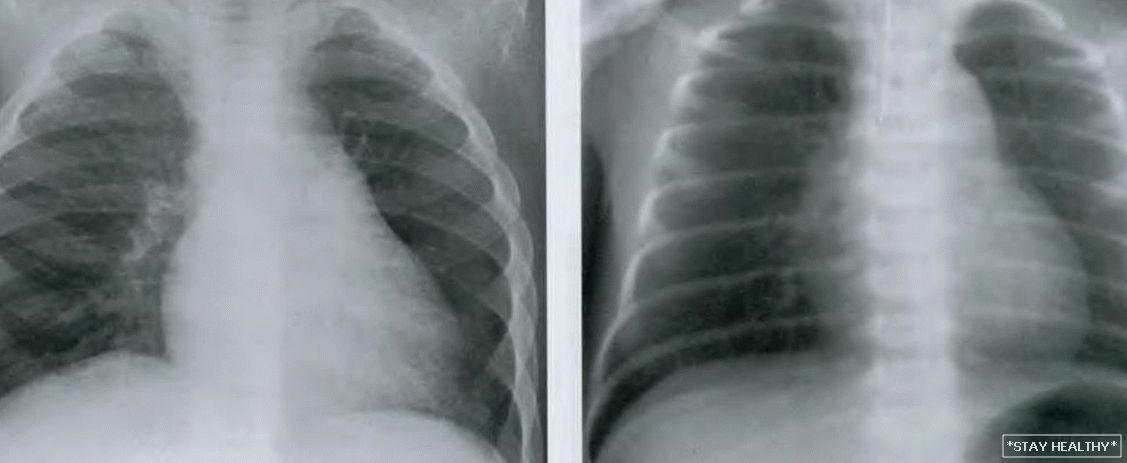

Снимок грудной клетки здорового ребенка: примеры и диагностика